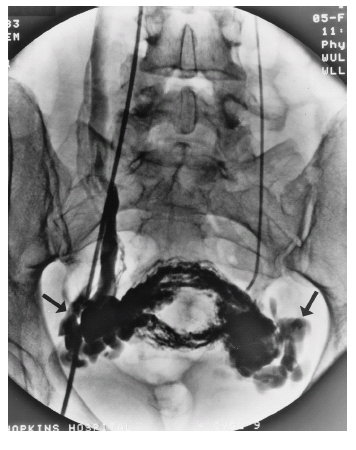

在详细的病史询问和体格检查后,进行超声、CT、MRI、磁共振下血管造影(图19-3)、腹腔镜等检查均有助于盆腔静脉淤血综合征的诊断。影像学检查常同时发现其他异常表现,例如盆腔超声检查发现多囊卵巢(56%盆腔静脉淤血综合征患者合并多囊卵巢)、子宫腺肌症患者。生殖器官静脉造影可以了解盆腔静脉淤血综合征患者静脉曲张的程度(图19-4)。股静脉或颈静脉穿刺插管成功、造影显示左侧卵巢静脉后不立即置入导管,以避免漏诊胡桃夹综合征。在左卵巢静脉附近的静脉血管内注射造影剂,同时患者直立位做Valsalva动作,观察是否存在左卵巢静脉血液返流,如果未发现血液返流,盆腔静脉淤血综合征诊断可能性小,从该点向右卵巢静脉内置管,如果无法快速置管或未见血液返流,则可能无静脉返流存在或返流的程度轻,可以结束检查。如发现存在明显的左卵巢静脉返流(返流的卵巢静脉直径大于8mm),盆腔静脉淤血综合征诊断可能性大。明确盆腔静脉淤血综合征的诊断后如准备进行栓塞治疗需在异常静脉管腔内置管。由于扩张的静脉质地脆,易产生痉挛,操作过程应小心谨慎并间断注入造影剂选择正确的置管路径同时可进一步观察是否合并存在股静脉或阴部静脉的曲张。

图19-4 数字减影血管造影图片箭头提示盆腔曲张的血管丛